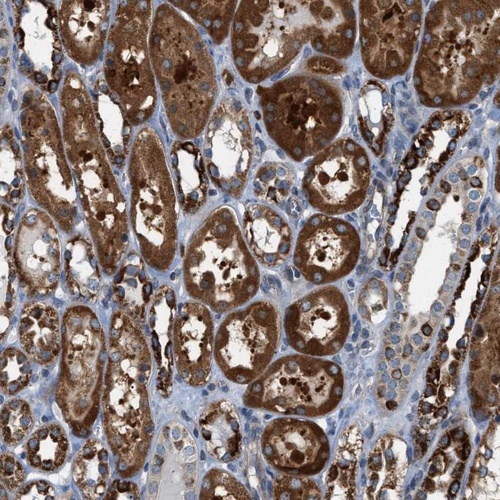

Immunohistochemical staining of human kidney shows strong cytoplasmic positivity in tubular cells.